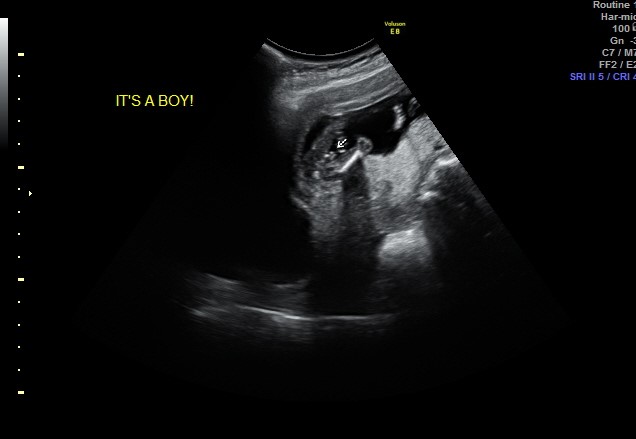

I had an early elective ultrasound yesterday at 14 weeks and 5 days. Baby was measuring at 15 weeks and the tech said boy. Is she correct? Am I having a boy??

I'm really hoping it's a boy!Attachment 41053Attachment 41052

It looks boyish but I know the 14th week can be so tricky with gender determination, and even the 15th week is early. When will you be getting another scan?

I had two 15 week gender scans en this is a boy! Obvious

it looks boyish but being only 14w makes me unsure, if that was a 16w pic id be saying 100% boy :) fingers crossed this is your boy!!

funnily enough ive just seen another thread with a 14w potty shot where the tech guessed 70% girl, i dont trust 14w potty shots i think it is too early but.. that thread showed a potty shot with nothing between the legs, compare it to yours and there is a world of difference, fingers crossed for you! :)

To the original poster: This is a boy to me. Congrats! I have done a lot of googling on this and I saw a 14 min lecture by Dr. Mahir on youtube about gender determination.

Thought I would update everyone. Blood work confirmed that I'm having a boy!! I'm over the moon excited! :D